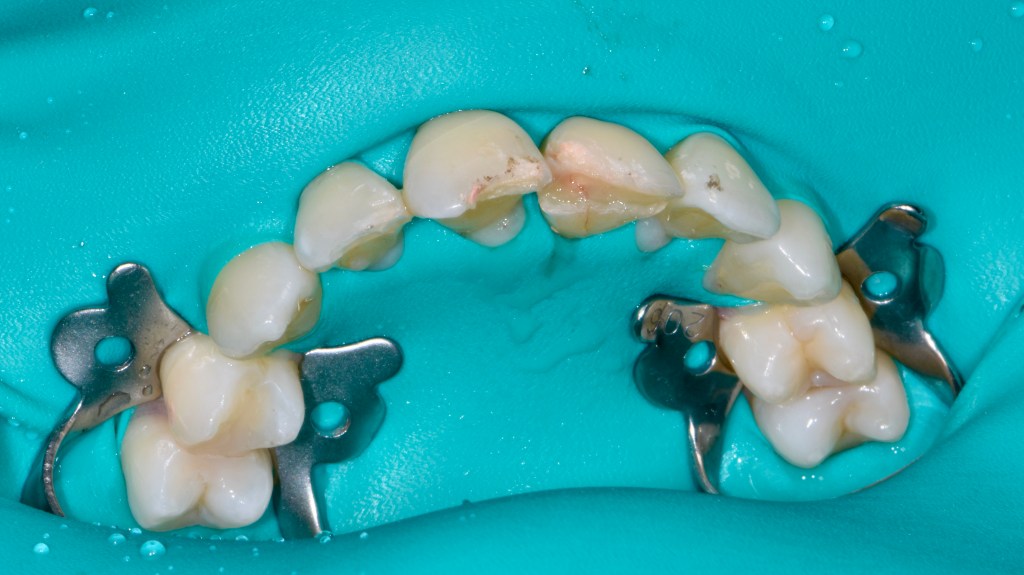

Implant Bridge and Ceramic Crowns